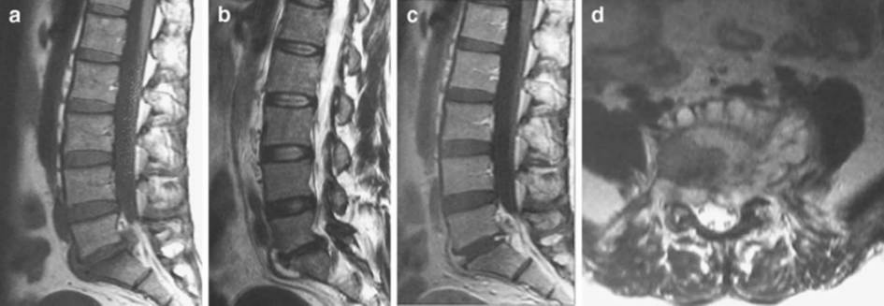

腰椎布鲁氏菌性脊柱炎早期MRI表现

A  T1 L4呈低信号;B  T2  L4呈高信号。椎体前方有轻度、边界不清的骨破坏,无硬膜外脓肿。

布鲁氏菌性脊柱炎MRI a T1;b T2;c T1增强;d T2轴位增强 MRI 显示S1上终板、椎体周围骨水肿、硬膜外脓肿。,可见椎间盘周围增强。